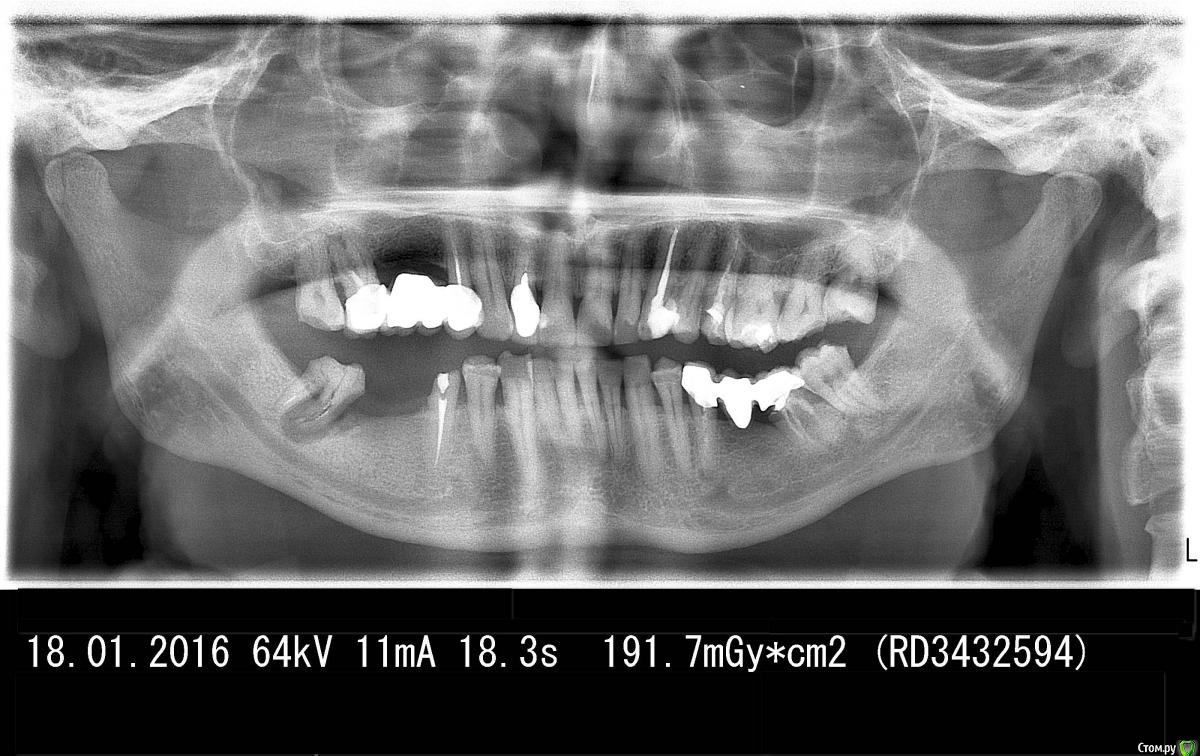

IvanK Опубликовано 18 января, 2016 Поделиться Опубликовано 18 января, 2016 выложите панорамный снимок (ОПТГ) Ссылка на комментарий

alex380 Опубликовано 18 января, 2016 Автор Поделиться Опубликовано 18 января, 2016 выложите панорамный снимок (ОПТГ)Вот, сделал снимок. Пора обсуждать имплантацию, что ставить, где и у кого делать, и сколько будет стоить. Ссылка на комментарий

Гарриевич Опубликовано 18 января, 2016 Поделиться Опубликовано 18 января, 2016 противоположная сторона тоже тоже требует леченияимплантация необходима в области 6 и 7 Ссылка на комментарий

IvanK Опубликовано 18 января, 2016 Поделиться Опубликовано 18 января, 2016 Консультация ортодонта и ортопедаудаление 28, 38,37, 48повторное лечение, протезирование 17,14,12, 23,25, 35,45Протезирование с опорой на имплантаты / съемное протезирование все, что я могу сказать без очного осмотра, естественно, возможны коррективы.. Ссылка на комментарий